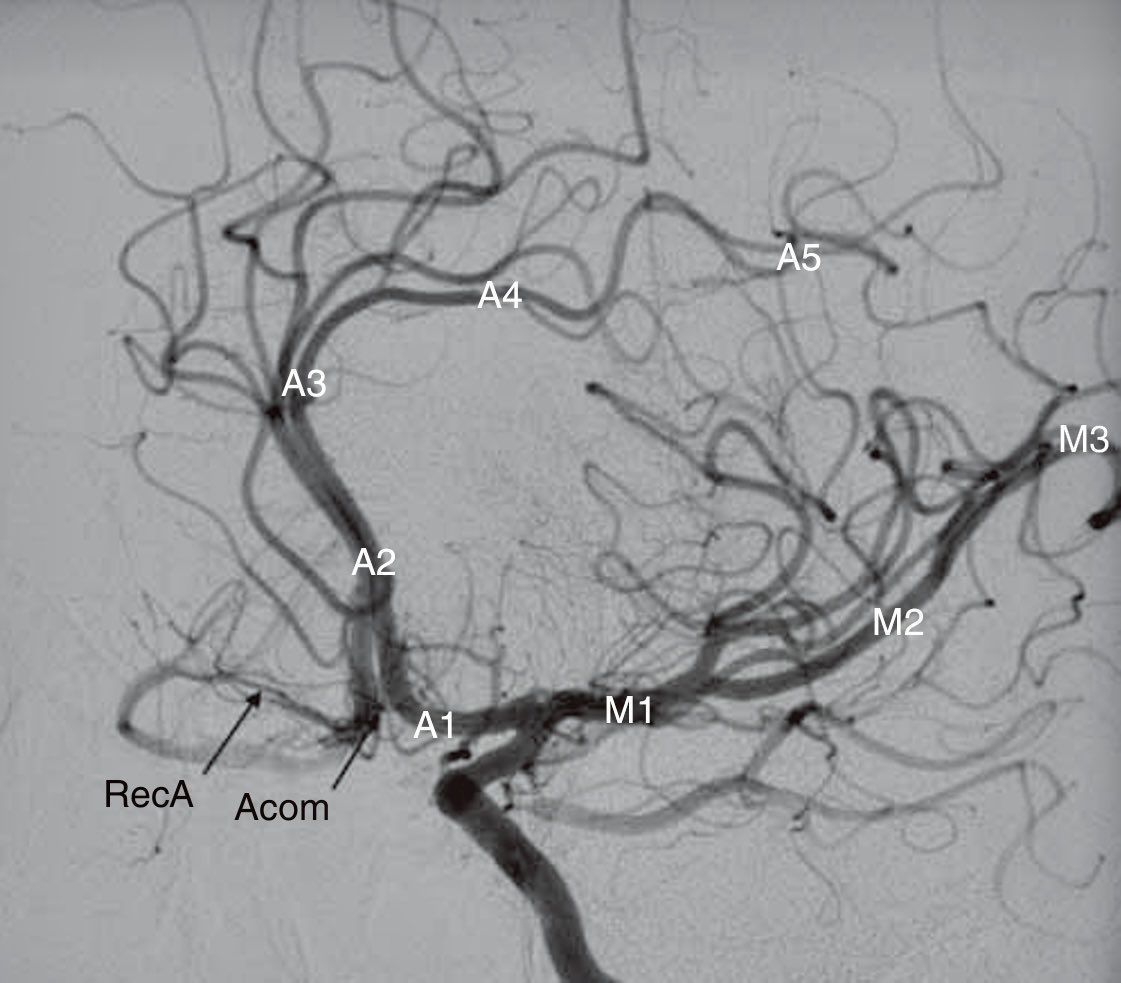

An oblique view demonstrates the classification schemes of the anterior cerebral artery and the middle cerebral artery. A, Anterior cerebral artery M, Middle cerebral artery RecA, Recurrent artery of Heubner Acom, Anterior communicating artery

An oblique view demonstrates the classification schemes of the anterior cerebral artery and the middle cerebral artery.

A, Anterior cerebral artery

M, Middle cerebral artery

RecA, Recurrent artery of Heubner

Acom, Anterior communicating artery